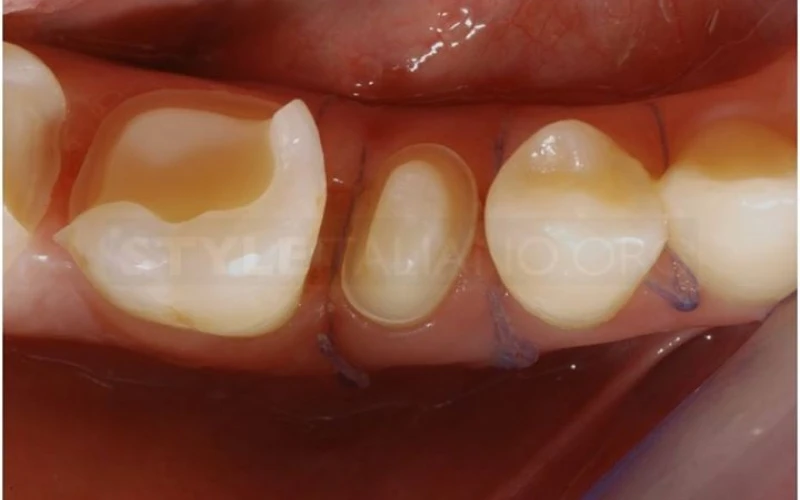

5. Sau khi gỡ đê cao su, thực hiện phẫu thuật làm dài thân răng lâm sàng răng 4.5 để tạo khoảng sinh học đúng.

6. Đặt đê cao su và thực hiện điều trị tủy răng 4.5. Bắt đầu phục hình sơ bộ cho các răng.

7. Phục hình răng 4.5 với chốt: thử chốt.

8. Phục hình răng 4.5 với chốt: gắn chốt bằng dual cement.

9. Phục hình răng 4.5 với chốt: tái tạo bằng phục hồi quang trùng hợp.